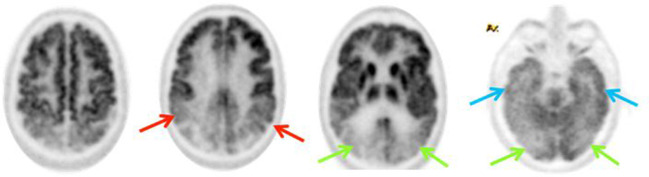

Nella forma classica, l’ipometabolismo inizia solitamente nelle regioni della Default Mode Network (DMN). Le aree precocemente colpite includono la corteccia cingolata posteriore e il precuneo.14 Successivamente, il deficit si estende alle cortecce associative temporo-parietali (giro angolare, giro temporale medio e inferiore) e, nelle fasi più avanzate, ai lobi frontali (cortecce prefrontali associative).

Un segno distintivo dell’AD è il risparmio relativo della corteccia motoria e sensoriale primaria, della corteccia visiva primaria, dei gangli della base, del talamo e del cervelletto.

(B) PCA: ipometabolismo nelle aree occipitali e parietali e un relativo ipermetabolismo nel lobo frontale.

(C) Variante logopenica dell’afasia primaria progressiva (lvPPA): mostra ipometabolismo nelle aree temporali e parietali sinistre.

(D) AD disesecutiva (dAD): ipometabolismo nella corteccia associativa eteromodale e ipermetabolismo nelle cortecce sensoriali e motorie primarie.

(E) Variante comportamentale dell’AD (bvAD): ipometabolismo nelle cortecce frontali, temporali mediali e del cingolo.

La DLB si manifesta spesso con ipometabolismo parieto-occipitale, simile alla PCA, ma con una distinzione fondamentale riguardante il cingolo posteriore.

Cingulate Island Sign (CIS): si riferisce alla relativa preservazione del metabolismo nella corteccia cingolata posteriore nonostante il marcato ipometabolismo nel precuneo e nelle aree occipitali circostanti.18

Il CIS ha una specificità estremamente elevata (fino al 100% in alcuni studi) per la DLB rispetto all’AD, dove il cingolo posteriore è tipicamente una delle prime aree a diventare ipometaboliche.19